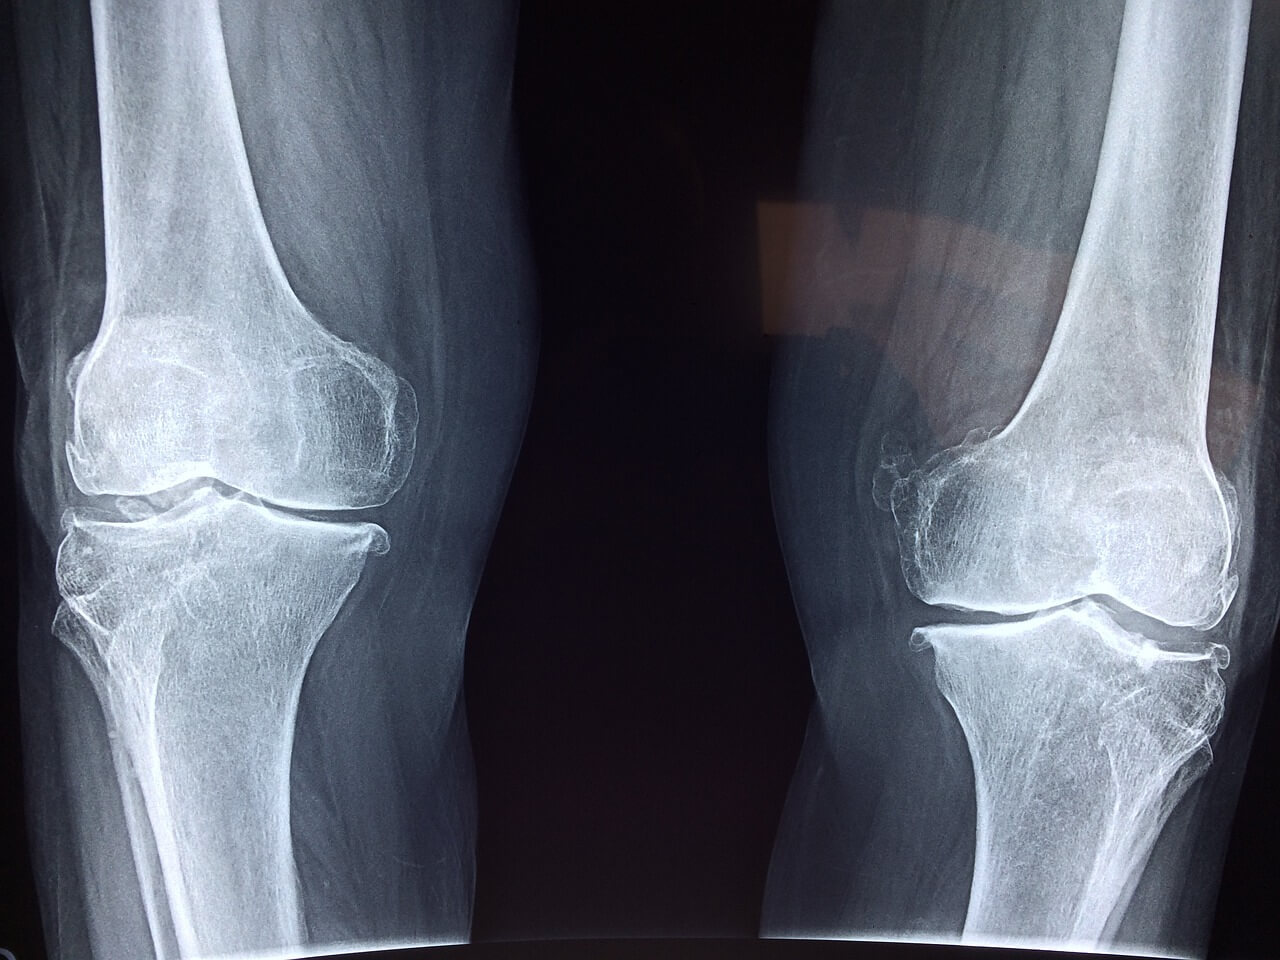

60대에 접어들면서 관절 건강은 더욱 중요해집니다. 요즘은 30대부터 직업병 또는 성인병으로 관절 통증이 발생하기도 합니다. 일찍부터 관절 영양제를 통해 건강한 관절을 챙기는 것이 좋습니다. 관절 영양제는 자유로운 움직임과 활동적인 노후 생활을 즐길 수 있는 열쇠입니다.

관절 건강을 지원하는 영양제는 다양하게 시장에 나와 있습니다. 그 중에서도 글루코사민과 콘드로이틴은 관절 연골의 건강을 보호하고 염증을 줄이는 데 도움을 줄 수 있습니다. 또한 오메가-3 지방산은 관절 염증을 감소시키고 유연성을 증진시키는 데 도움이 됩니다. 관절 영양은 평소에 관리하는 것이 중요하며, 나이가 들수록 쉽게 회복되기 어려운 관절과 관련된 사안은 반드시 가볍게 여기지 않아야 합니다.

관절 영양제 추천 30대가 넘는 성인이거나 60대가 넘으셨다면 관절 영양제 복용을 통해 얼마든지 건강한 관절을 유지하며 삶을 즐기실 수 있습니다. 더불어 올바른 식습관과 꾸준한 운동, 적절한 관절 영양제 복용은 풍요로운 노후를 위한 중요한 요소입니다. 지금 관절 상태를 점검해보시고, 관절 가동성 또는 통증 등 문제가 있다면 지체없이 가까운 병원을 내방하셔서 상담받아보시기 바랍니다.